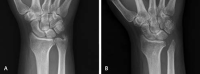

The distal radioulnar joint (DRUJ), the articulation between the sigmoid notch of the radius and the distal ulna, plays a pivotal role in stability and load bearing and allows for pronation and supination of the forearm. Osteoarthritis (OA) of the DRUJ commonly occurs due to distal radius trauma but may also be the result of conditions such as joint instability, septic arthritis, or primary OA. It is initially managed with conservative therapy, but surgery is often considered when nonoperative methods fail. The surgical approaches available to treat this pathology have grown over the years. The procedures have generally favorable outcomes, each with their own unique complications and considerations. This paper comprises a review of the outcomes and complications for the different procedures commonly used to surgically treat DRUJ OA.